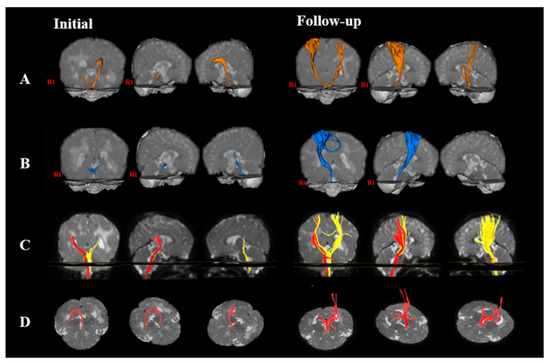

3.1. Change of the Neural Pathway

| CST | CRP | ||||

|---|---|---|---|---|---|

| Initial | Follow-Up | Initial | Follow-Up | ||

| FA | Right | 0.263 | 0.330 | 0.350 | 0.290 |

| Left | 0.330 | 0.398 | 0.307 | - | |

| MD | Right | 1.520 | 1.006 | 0.943 | 0.002 |

| Left | 1.110 | 0.987 | 0.012 | - | |

| TV | Right | 244.000 | 2508.000 | 152.000 | 183.000 |

| Left | 507.000 | 354.000 | 3920.000 | - | |